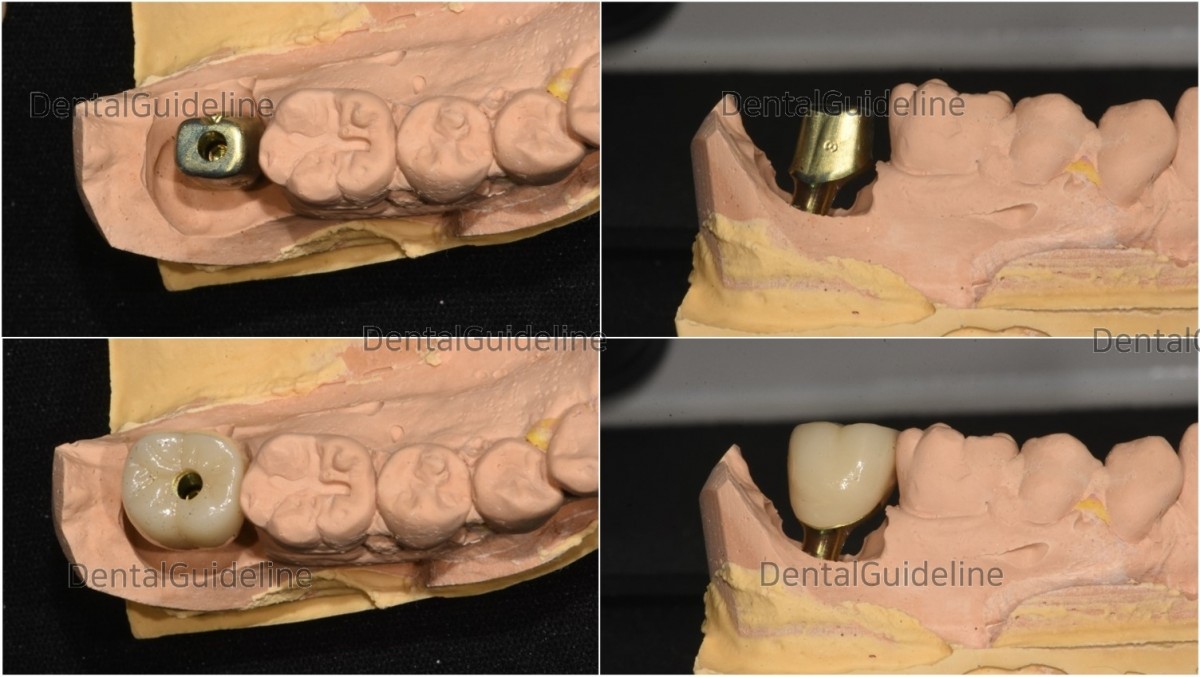

12. Customized abutment and crown(zirconia) from the dental lab..

13. Intraoral photo on the day the prosthesis is completed.

14. Adjustment of the implant support crown.

15. Final cementation and the access hole was filled with composite resin.